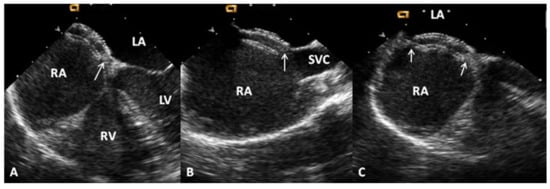

5.3. Sinus Venosus ASDs